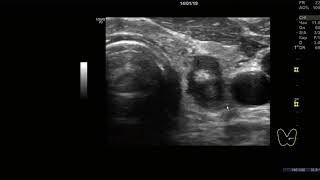

Онкомаркер CA125: рак яичника или нет?